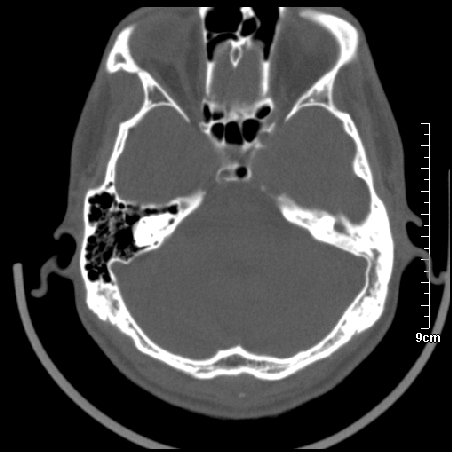

病例1

m/46y 头晕.耳鸣半月余 有乳突炎病史

病例2

m/27

胆脂瘤是是以鳞状上皮内衬充满角质化碎片的囊,随着角化屑片的不断堆积,肿块逐渐增大,胆脂瘤可为先天性(2%)或后天性(98%)。胆脂瘤有感染史。中耳内的鳞状上皮通常有外耳道的上皮通过一鼓膜的缺损移行至中耳,其他的原因包括鳞状上皮化生。由于欧氏管的功能不全所引起的中耳负压可产生上鼓室鼓膜松弛部的牵引性开袋。继而发展成胆脂瘤。成年人胆脂瘤时乳突常发育差,而儿童常有广泛性乳突气化,这种气化可导致胆脂瘤的更广泛的乳突扩散。后天性胆脂瘤患者大多数存在骨质破坏。

松弛部胆脂瘤有中央性穿孔或后上部牵引口袋所致。紧张部胆脂瘤经常侵蚀听小骨并引起传导性耳聋。

中耳胆脂瘤有两个重要并发症:一是面神经管的水平段受暴露,二是外侧半规管受侵蚀产生瘘管。面神经在ct上难以显示或不可能显示,除非其周围有空气包绕或有良好轮廓的骨性覆盖。胆脂瘤还可合并感染,产生于急性中耳炎.乳突炎所描述的那些合并症。